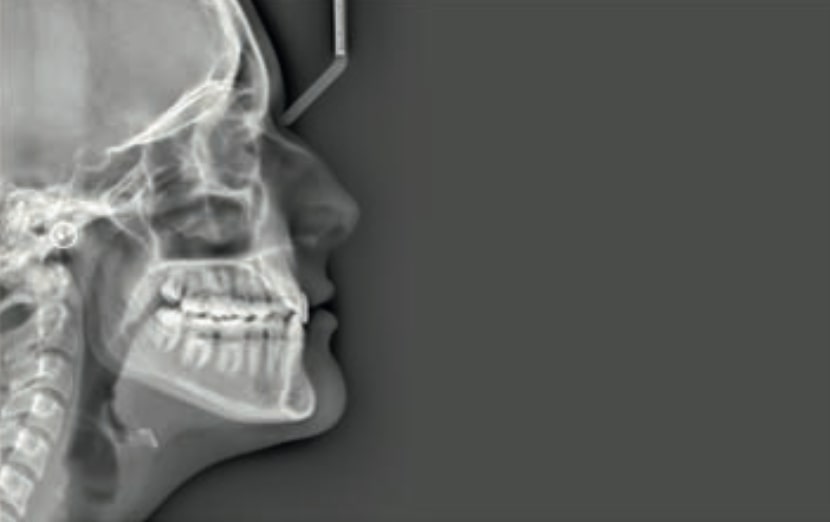

Chief complaint: The patient, a 19-year-old woman, was evaluated to undergo orthodontic treatment using the Angel Aligner Pro system. She presents with a skeletal Class III, mesofacial, with a dental Class III malocclusion and a 2 mm deviation of the lower midline to the left. Teeth 33 and 43 are out of the arch and cortical bone, with a crossbite issue on tooth 33. Fortunately, no functional issues affecting swallowing or breathing have been detected. The patient’s motivation for starting treatment was a general review of her dental and aesthetic health. The soft tissue analysis reveals mandibular protrusion that influences her facial profile. This diagnosis highlights the need for a comprehensive approach to address dental and skeletal misalignments, improving both the patient’s functionality and facial aesthetics.

- Skeletal class III

- Soft Tissue Analysis: Jaw protrusion